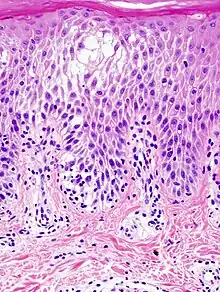

Espongiosis es un término que se emplea en medicina para describir la existencia de edema intercelular en la capa de células de la piel llamada capa de Malpigio o capa esponjosa. La espongiosis puede observarse en numerosas enfermedades que afectan a la piel.[1][2][3][4]

La espongiosis se observa cuando se estudian muestras de una biopsia de piel a través del microscopio, En la capa de Malpigio, las células están más separadas de lo normal y pueden formarse pequeñas vesículas por acumulación de líquido, observándose además la presencia de células inflamatorias como linfocitos.